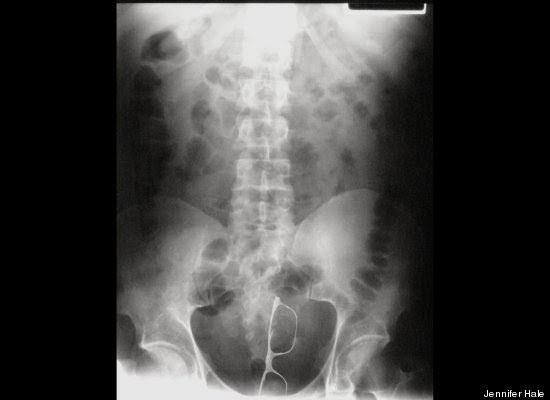

"Stack Up!" es una muy divertida colección de 100 imágenes de rayos X que muestra cuerpos extraños ingeridos o insertados en el cuerpo humano, tanto por accidente o de forma voluntaria, aunque se haga difícil imaginar el motivo de algunas de tales inserciones.

"Tenía las manos ocupadas", "me caí encima", son algunas de las excusas que los profesionales de la salud escuchan de los pacientes que llegan a los hospitales con "cuerpos extraños extrañamente metidos en el cuerpo".

Redactado de manera humorística, el libro se pregunta cómo un teléfono celular puede haber ido a parar al sitio de la anatomía del propietario donde nunca da el sol, respondiéndose que, probablemente, estuviera en modo vibrador.